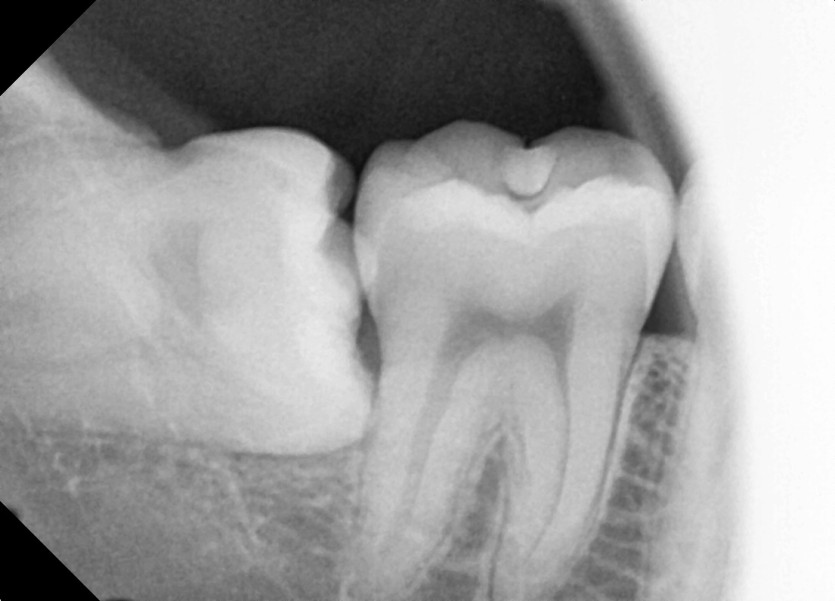

#18,48 사랑니 발치

구강외과 전문의가 당일 발치했습니다.